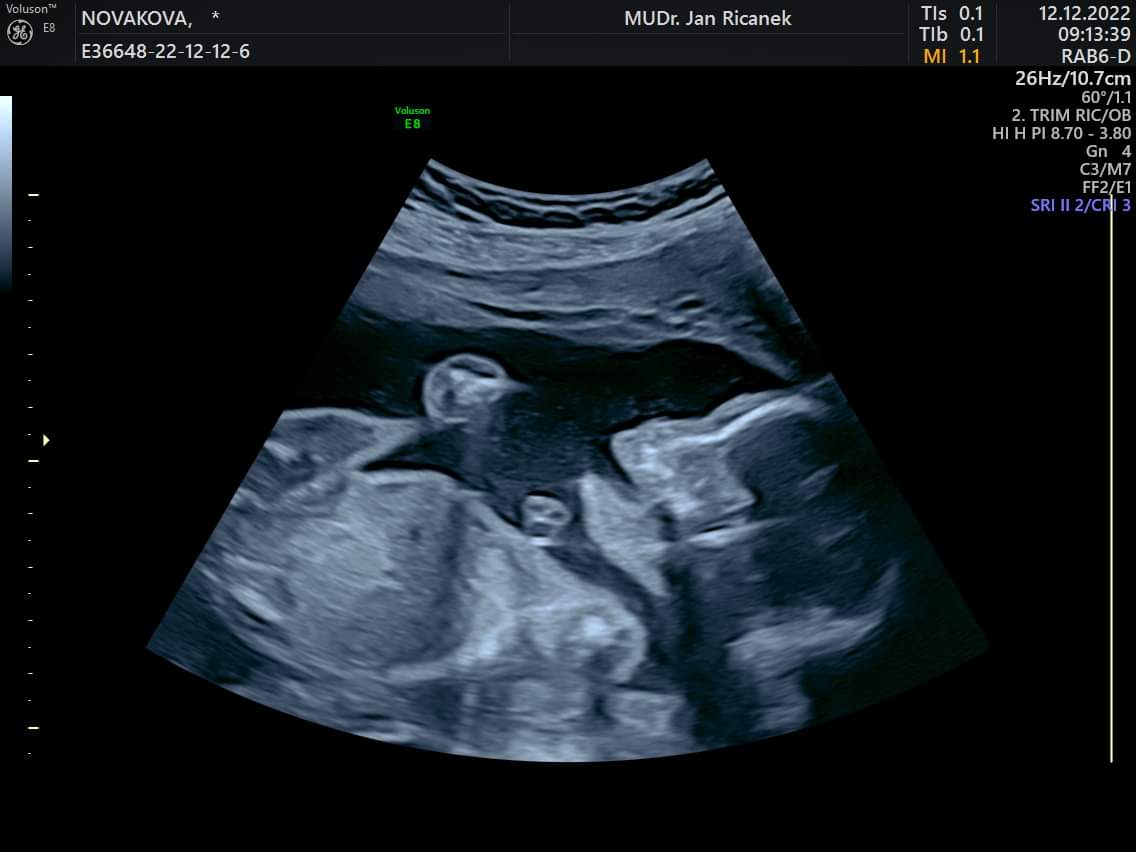

Tak holky dnes 2. trimestralni screening a vse v poradku 🙂 <3

Já mám taky hezkou fotku z poslední kontroly 🤣🤣🤣 má krásnou páteř